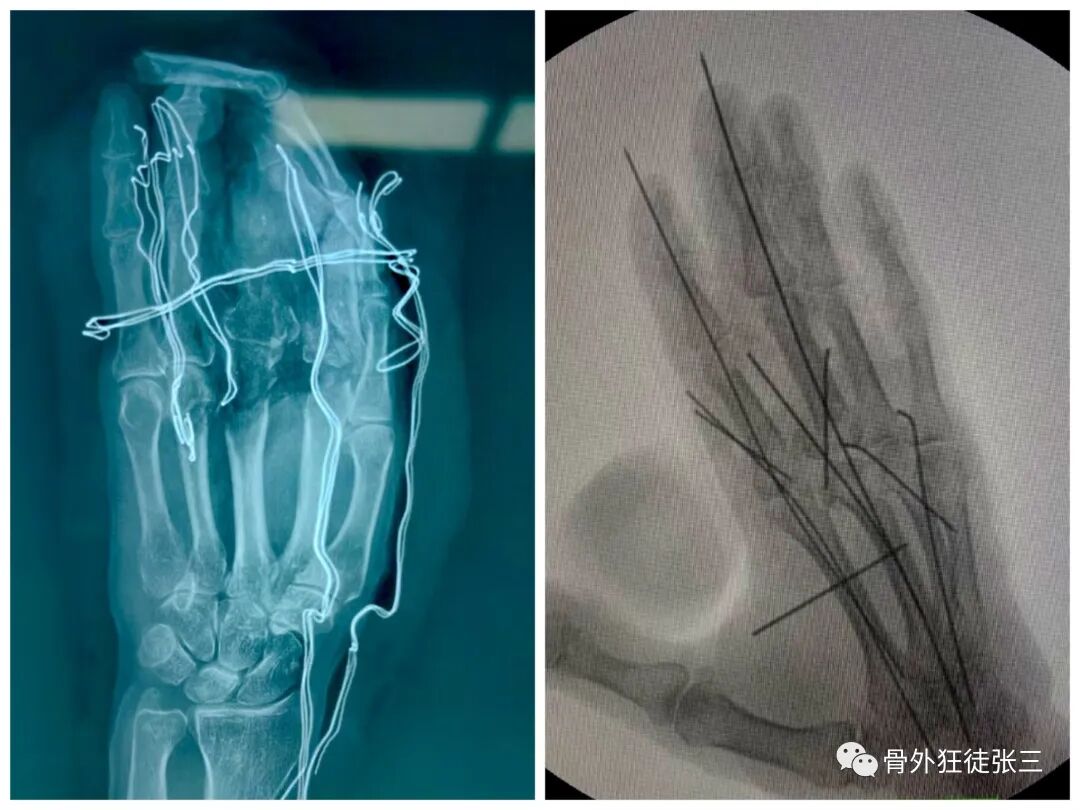

病例6,开放性第2345掌骨骨折,克氏针支架

病例7,开放性掌骨,指骨骨折,克氏针内固定